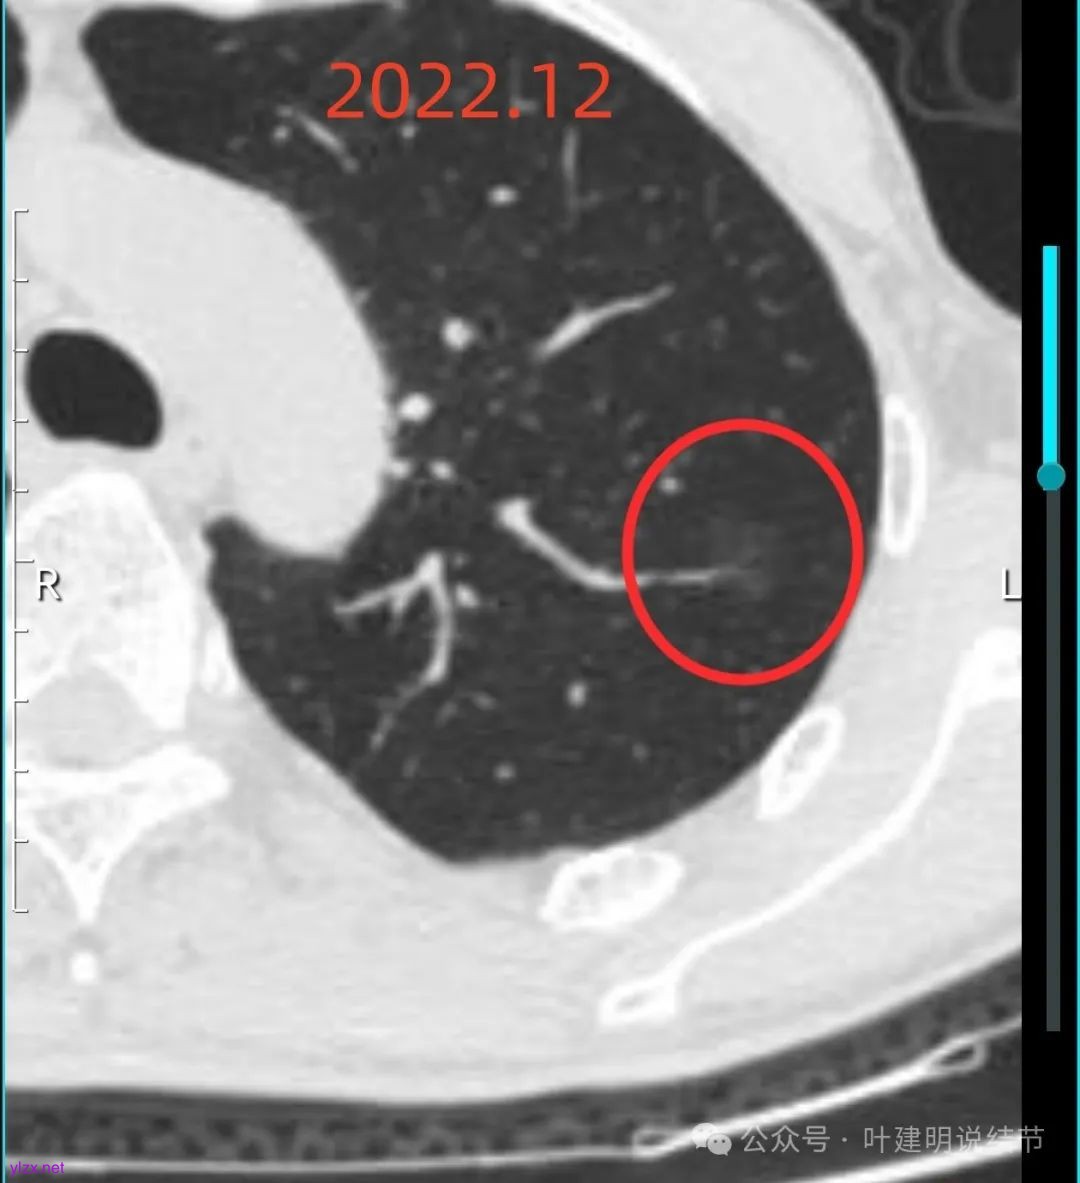

我们先来看2022年12月时的影像:

左上这个病灶是淡磨玻璃密度,虽然较淡但轮廓与边界却较为清楚,也有血管进入,倒是要考虑恶性范畴的,但这种密度仍是原位癌可能性较大。

病灶内没有明显实性成分,整体轮廓较清。